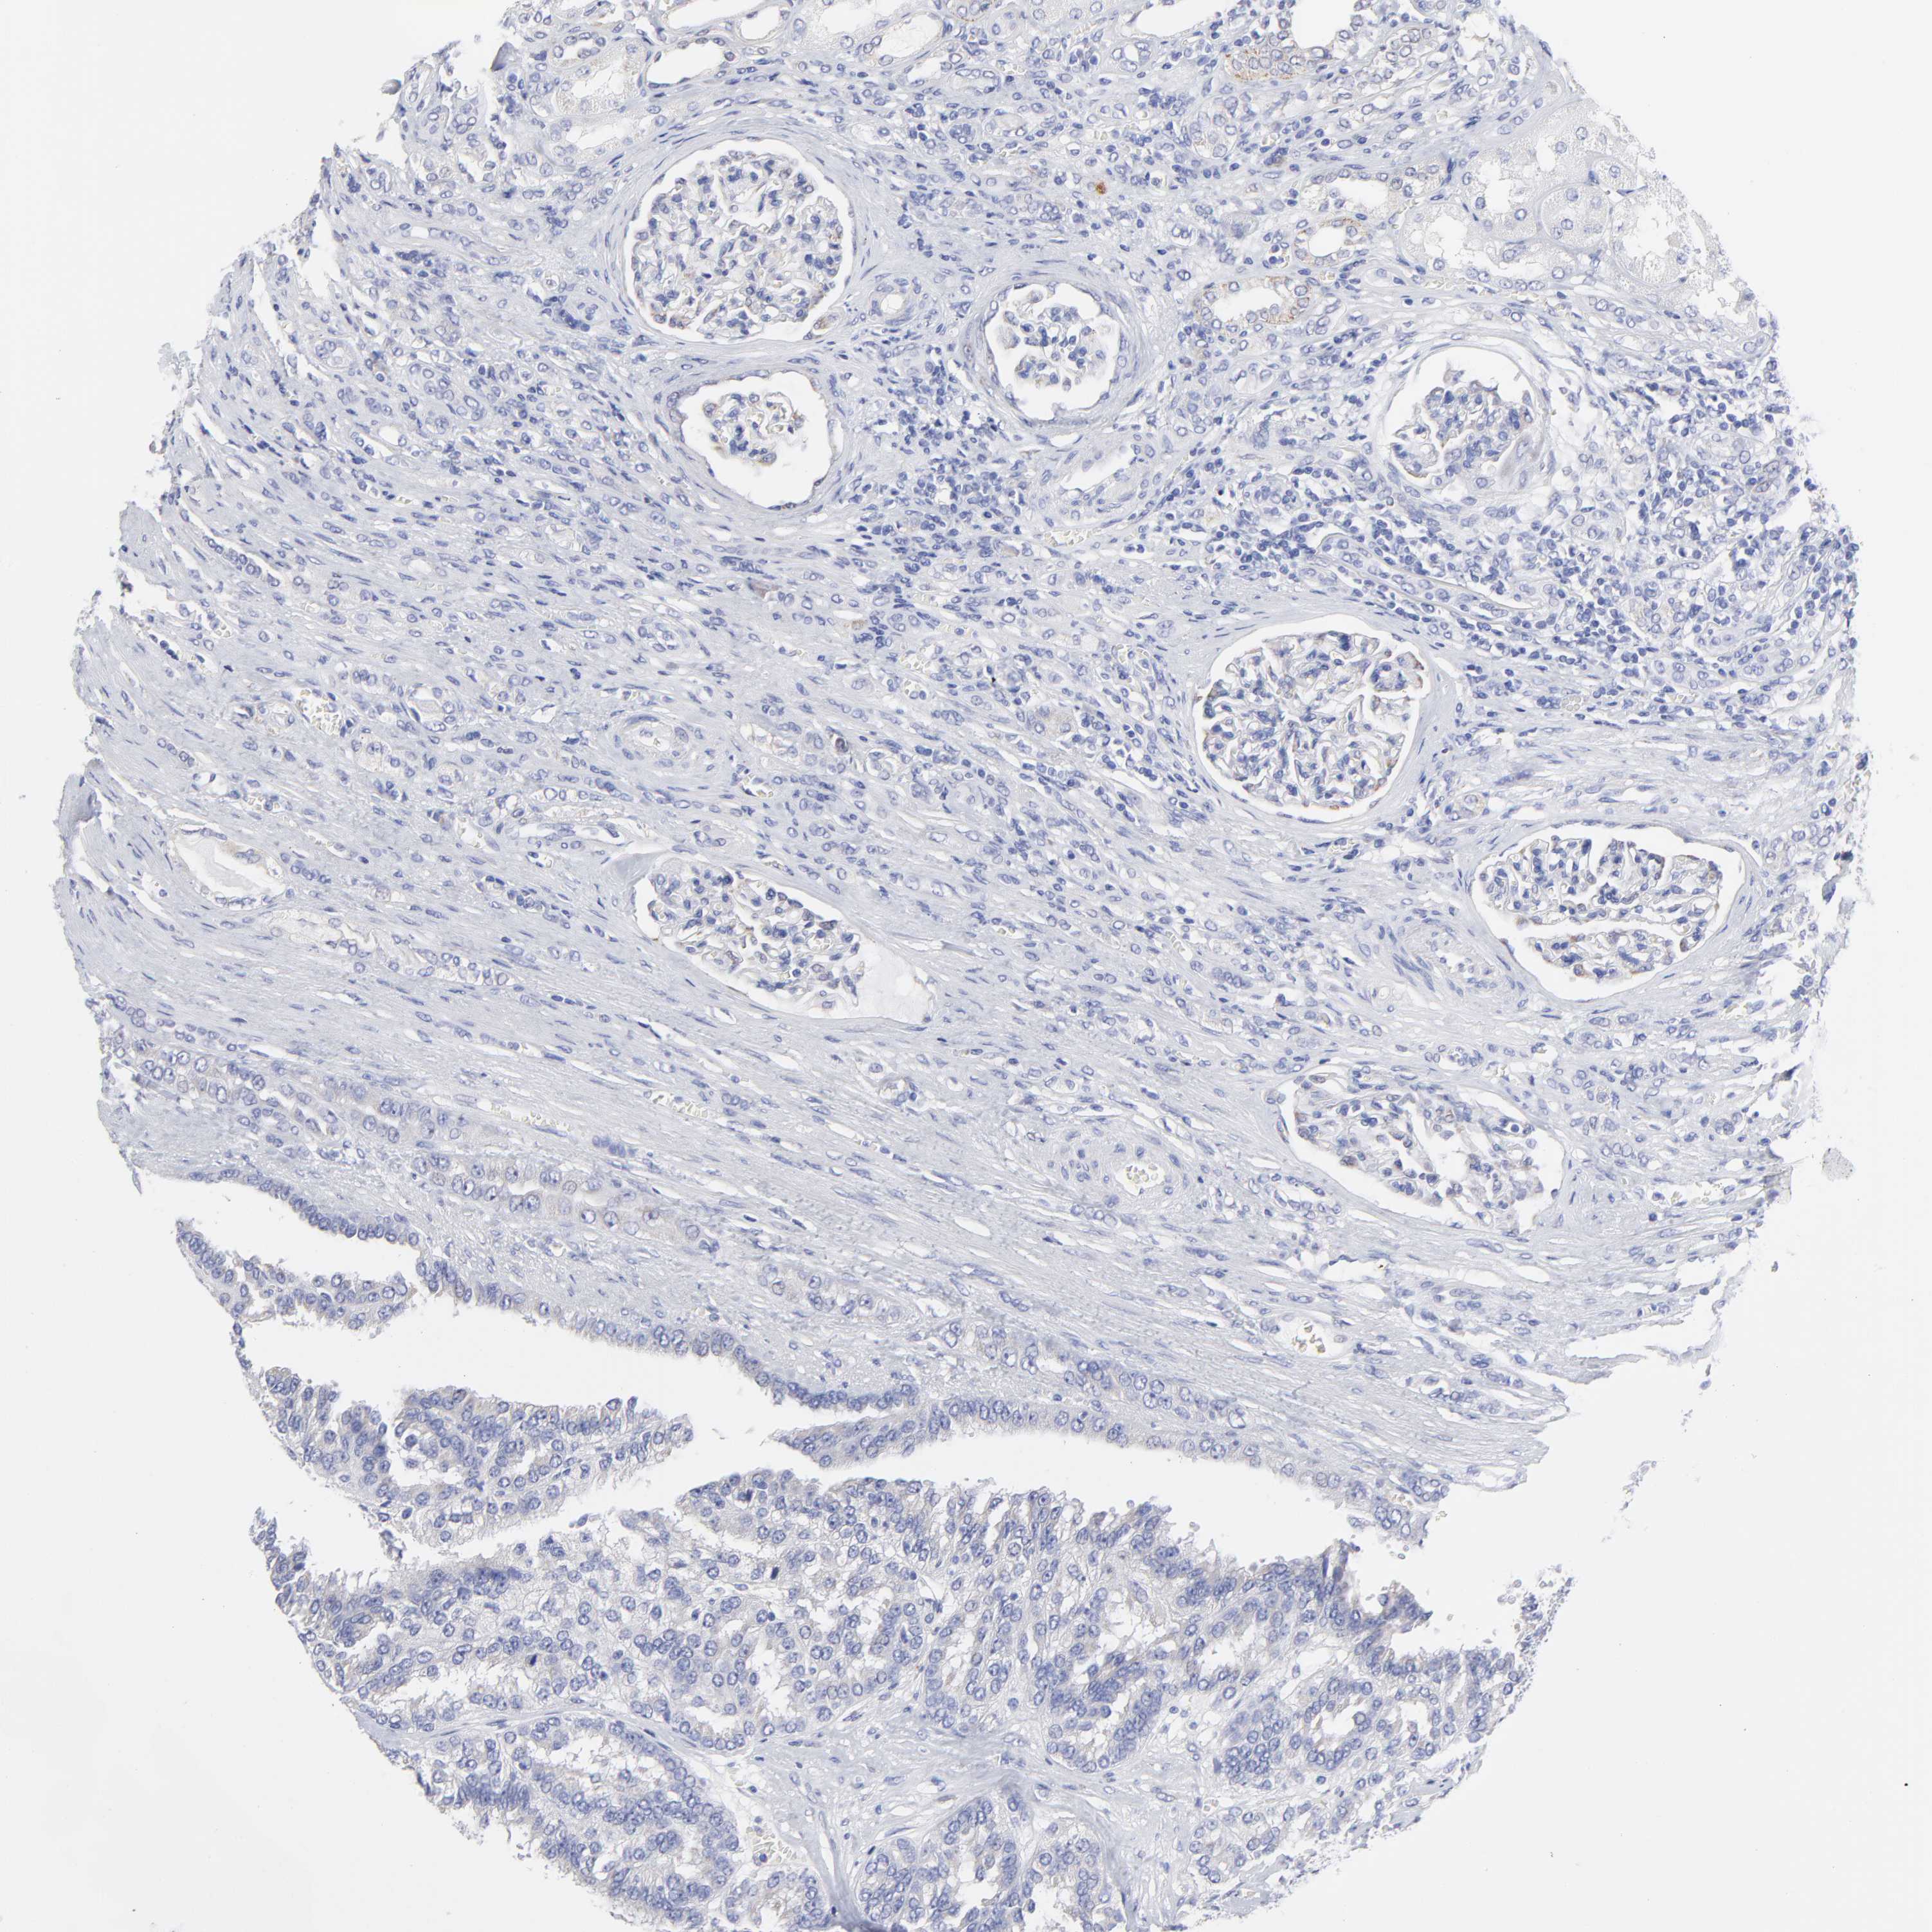

KIDNEY RENAL CLEAR CELL CARCINOMA (VALIDATION) - Interactive survival scatter ploti

The Survival Scatter plot shows the clinical status (i.e. dead or alive) for all individuals in the patient cohort, based on the same data that underlies the corresponding Kaplan-Meier plots. Patients that are alive at last time for follow-up are shown in blue and patients who have died during the study are shown in red.

The x-axis shows the expression levels (FPKM) of the investigated gene in the tumor tissue at the time of diagnosis. The y-axis shows the follow-up time after diagnosis (years). Both axes are complimented with kernel density curves demonstrating the data density over the axes. The top density plot shows the expression levels (FPKM) distribution among dead (red) and alive patients (blue). The right density plot shows the data density of the survived years of dead patients with high and low expression levels respectively, stratified using the cutoff indicated by the vertical dashed line through the Survival Scatter plot. This cutoff is automatically defined based on the FPKM cutoff that minimizes the p-score. The cutoff can be changed by dragging the vertical line or by entering a cutoff value in the square labeled "Current cut-off".

Under the Survival Scatter plot the p-score landscape (black curve; left axis) is shown together with dead median separation (red curve; right axis). Dead median separation is the difference in median mRNA expression between patients who have died with high and low expression, respectively. It is calculated as follows: median FPKM expression of dead patients with high expression - median FPKM expression of dead patients with low expression. This is intended to aid the user in visually exploring custom cutoffs and the associated p-scores and dead median separation.

Individual patient data is displayed and can be filtered by clicking on one or more of the category buttons on the top of the page. Categories describing expression level and patient information include: high, low, alive, dead, female, male and tumor stages. The scale of the x-axis can be toggled between linear and log-scale by clicking on the "x log" button. Mouse-over function shows TCGA ID, patient information and mRNA expression (FPKM) for each patient.

& Survival analysisi

Kaplan-Meier plots summarize results from analysis of correlation between mRNA expression level and patient survival. Patients were divided based on level of expression into one of the two groups "low" (under cut off) or "high" (over cut off). X-axis shows time for survival (years) and y-axis shows the probability of survival, where 1.0 corresponds to 100 percent.

DUSP9 is not prognostic in Kidney Renal Clear Cell Carcinoma (validation)

: 0.14

Average pTPM 1.8

Number of samples 100